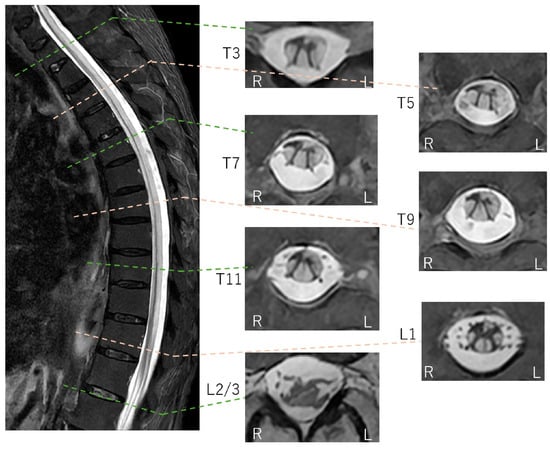

Cervicothoracic MRI findings. Hyperintensity on short tau inversion recovery fast spin-echo (STIR FSE) (A,B) and T2-weighted imaging (C) corresponds to the longitudinally extensive diffusion-restricted lesions observed along the spinal cord. These axial sections reveal diffuse involvement of the entire white matter circumference and robust diffusion restriction (low ADC), distinguishing the pathology from the central gray matter target and isointense or increased ADC values typical of neuromyelitis optica spectrum disorder (NMOSD) [6,7]. Although the massive elevation of CSF myelin basic protein (>500 pg/mL) and positive oligoclonal bands indicate an extensive breakdown of the myelin sheath, the diagnosis of NMOSD and other inflammatory myelopathies was excluded by negative serology for anti-aquaporin-4 (AQP4), anti-myelin oligodendrocyte glycoprotein (MOG), and anti-glial fibrillary acidic protein (GFAP) antibodies, combined with a lack of cerebrospinal fluid (CSF) pleocytosis and the clinical attribution of emesis to intestinal perforation rather than an area postrema lesion.